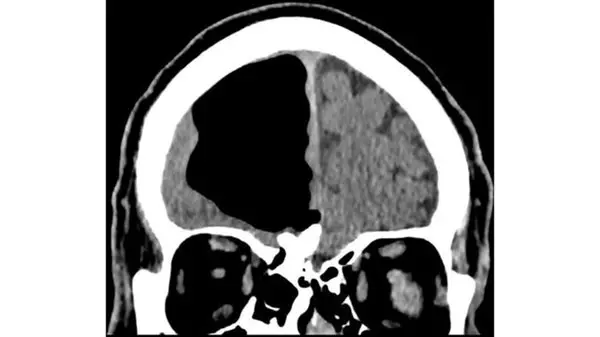

اگر چه نتیجه آزمایش خون این فرد طبیعی بود ولی تصویربرداریها از مغز او وجود یک حفره عجیب ۹ سانتی متری از هوا را در جمجمه نشان میداد.

این حفره به عنوان یک پنوماتوسل، حفرهای پرفشار از هوا، در سمت راست لوب پیشانی این فرد قرار گرفته است. این دسته از حفرهها معمولا در بیمارانی که سابقه جراحی مغز یا ابتلا به انواع مختلف عفونت را داشتهاند معمول است ولی اندازه آنها بسیار کوچکتر است.

اسکن مغزی همچنین یک تومور خوش خیم استخوانی و یک سکته ناقص در مغز او را نشان داد. به منظور درمان این حفره، پزشکان پیشنهاد جراحی به او را دادند که با توجه به خطرات ناشی از جراحی، این مرد ایرلندی پیشنهاد را نپذیرفت ولی در عوض قرار شد انواع مختلفی از داروها را برای کمک به پیشگیری از سکتههای آینده دریافت کند.